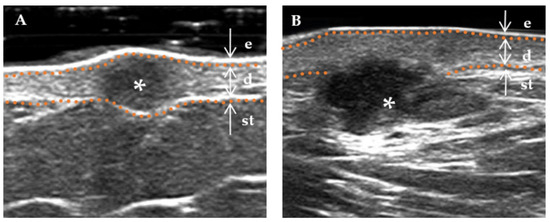

The following ultrasound features have been defined according to previous studies [3,15]. (a) Lesion size (including length and width): When visualized clearly, the length represents the maximum diameter of the lesion when measured in the longitudinal section, and the width represents the maximum diameter measured in the transverse section. (b) Thickness: The thickness should be measured in the thickest part of the lesion. (c) Shape (regular or irregular, with the former including the creeping form): The term “irregular”, in relation to skin lesions, refers to those with needle-like edges that penetrate the surrounding dermis or subcutaneous tissue. Conversely, a “regular” lesion is characterized by smooth edges without infiltration into the adjacent tissue [16]. (d) Morphology of the surface (concave, flat, and protuberance). (e) Boundary (Figure 2) of the base (well-defined and ill-defined). (f) Boundary (Figure 2) on both sides (well-defined and ill-defined). (g) Internal echogenicity (Figure 3): (homogeneous, heterogeneous). Homogeneous: the echogenicity was similar at all points in any direction of the mass. Heterogenous: the echogenicity distribution of each point in any direction of the mass was not consistent. (h) Echogenicity (isoechogenicity, hypoechogenicity, and mixed echogenicity). (i) Stratum basal (dermis, subcutaneous). (j) Doppler vascularity pattern (absent, sparsity, and profusion) (Figure 4).

Figure 3.

The internal echogenicity of DF lesions. * Indicates the precise location of the lesion on the ultrasound image. The skin layers are indicated by dotted orange lines, with arrows indicating a hyperechoic epidermis (e), an isoechoic dermis (d), and a subcutaneous tissue (st). (A) The internal echogenicity of the mass is homogeneously distributed: the mass exhibits a homogeneous low echogenicity pattern with similar echogenicity distribution in any direction. (B) The internal echogenicity of the mass is heterogeneously distributed: the core of the mass is hypoechoic compared to the cortex (cortical portion), which is more echogenic.